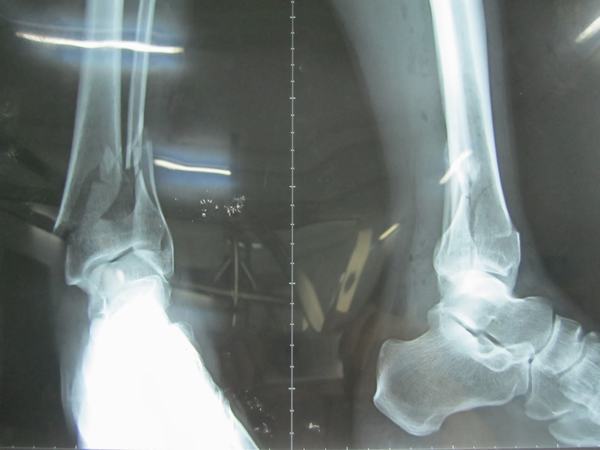

Gãy xương mác bao lâu thì lành là lo lắng chung của nhiều người. Thường sau khi chấn thương bạn cần bó bột và khoảng sau từ 5 đến 7 ngày bó bột thì xương sẽ bớt sưng hơn, phần bó bột lúc này có thể bị lỏng hơn. Khi đó các y bác sĩ sẽ thực hiện quấn thêm bột hay thay bột cho người bạn.

Và thời gian lành của một ca gãy xương mác sẽ phụ thuộc vào nhiều yếu tố khác nhau, tùy vào mức độ nghiêm trong của tình trạng xương bị gãy và độ tuổi của người bệnh. Tuy nhiên để xương mác có thể lành sau thời gian bó bột khoảng từ 3 đến 4 tuần hoặc có thể là 1 đến 2 tháng để xương có thể hoạt động như bình thường. Hơn nữa quá trình lành lại của xương mác có thể tốt hơn nếu bạn kết hợp giữa việc ăn uống lành mạnh và thực hiện các chăm sóc y tế, vật lí trị liệu hợp lý để việc phục hồi được diễn ra tốt nhất. Hơn nữa, những hoạt động nhẹ nhàng sau khi tháo bột cũng có thể giúp bạn nhanh phục hồi hơn. Nếu cần bạn có thể được bác sĩ kê thêm một số loại thuốc giảm đau để dễ vận động hơn.

Như vậy có thể thấy, tùy thuộc vào từng tình trạng của bệnh nhân mà quá trình lành xương có thể dài hay ngắn. Để phục hồi nhanh chóng bạn nên thường xuyên thăm khám bởi bác sĩ chuyên khoa để có phác đồ điều trị phù hợp.